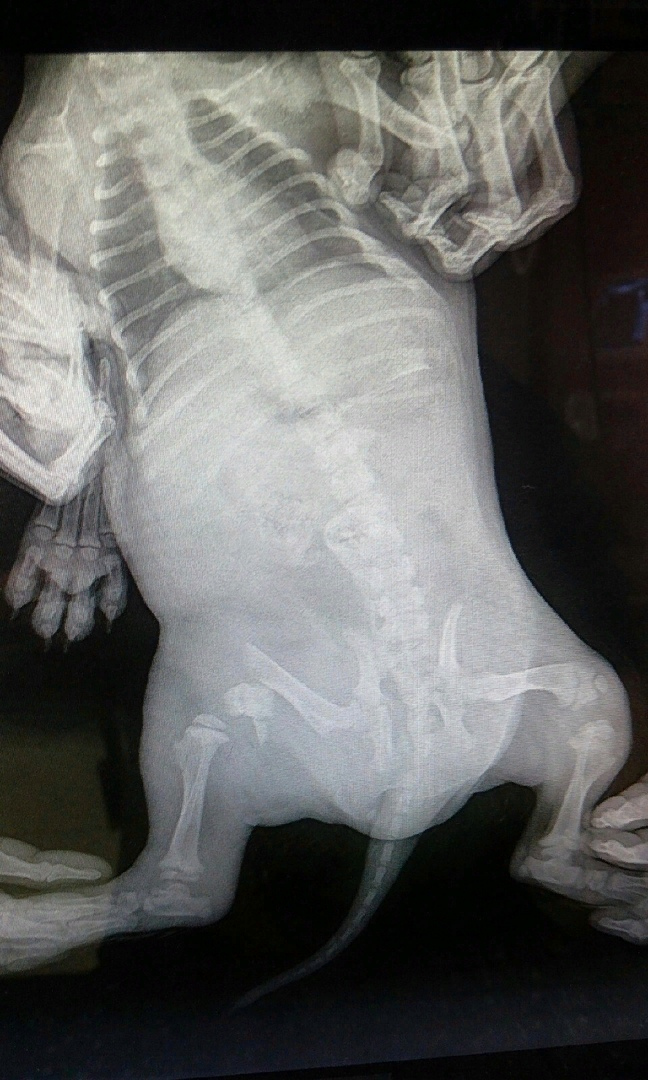

У бедолаги перелом лапы и обширный кровоподтек

Девушка проявила инициативу и доставила щенка в клинику, где по характеру травм врачи предположили, что двухмесячного щенка попросту пинали.

Эшли (так назвали малышку ) срочно требовалась сложнейшая операция, за которую берутся всего два-три ветеринара по всей Пензе.

Волонтеры срочно объявили сбор средств и собрали буквально за один день достаточную сумму денег на операцию и реабилитацию. Прооперировали ее Татьяна Кураева и ее муж Игорь. Оба хорошие врачи и просто люди с большой буквы, вышедшие на операцию в выходной день — любое промедление ухудшало состояние Эшли. Вдвоем они с мужем более двух часов собирали лапу.